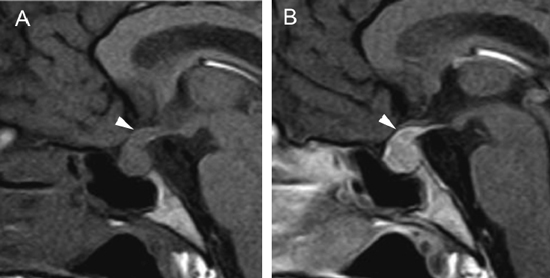

Figura 24 A y B. Hipofisitis, cortes sagitales, secuencias T1w antes y después de la inyección de Gadolinio, se observa aumento de volumen de la pituitaria y del infundíbulo, que muestran un refuerzo intenso y homogéneo (punta de flecha). Quiste de la bolsa de Rathke

Las imágenes más características en la RM son un aumento de tamaño simétrico de la glándula pituitaria, una estructura homogénea pre y postgadolinio, con refuerzo intenso después de la inyección de contraste paramagnético. (Figuras 24A y 24B).

La hipofisitis autoimmune (HA) puede imitar a los adenomas pituitarios no secretores y para diagnosticarse con certeza se requiere histología postbiopsia, lo que constituye un problema58. Aproximadamente un 40% de los pacientes con hipofisitis son erroneamente diagnosticados como macroadenomas pituitarios y sometidos a cirugía innecesaria.Los factores predictores de mayor utilidad para el diagnóstico son: la relación temporal con el embarazo, piso selar indemne, aumento de tamaño en forma simétrica de la hipófisis, aumento en la intensidad de señal después de la inyección de gadolinio, ausencia del foco de hiperseñal de la neurohipófisis, aumento de tamaño del tallo hipofisiario y edema mucoso, elementos que en conjunto alcanzan una sensibilidad de 92%, con especificidad de 99% y un valor predictivo positivo de 97% para el diagnóstico de hipofisitis autoinmune59.